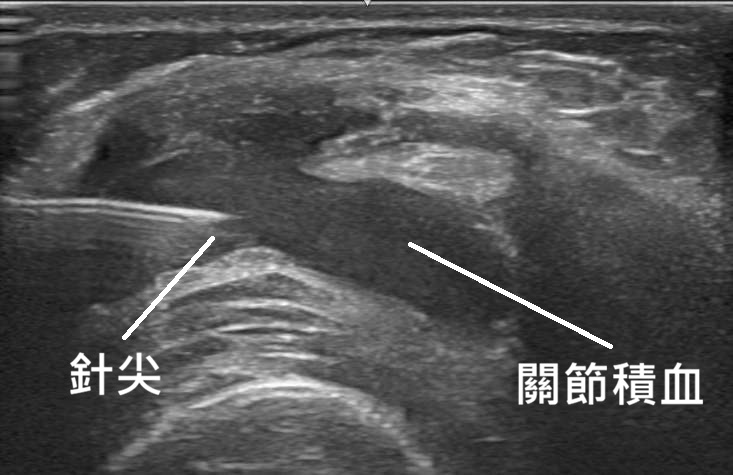

超音波: 可看到關節積血、韌帶腫脹,以及檢查是否合併半月板破裂或韌帶撕裂(這很常見,稱為惱人三重傷 Unhappy Triad),下圖為超音波導引下將積血抽吸出來。

治療方式: 急性期抽出關節積血。接著使用 PRP (高濃度血小板) 超音波導引下精準注射到撕裂的韌帶,促進癒合。最重要的是強化腿後肌及股四頭肌,讓強壯的肌肉代償韌帶的功能。